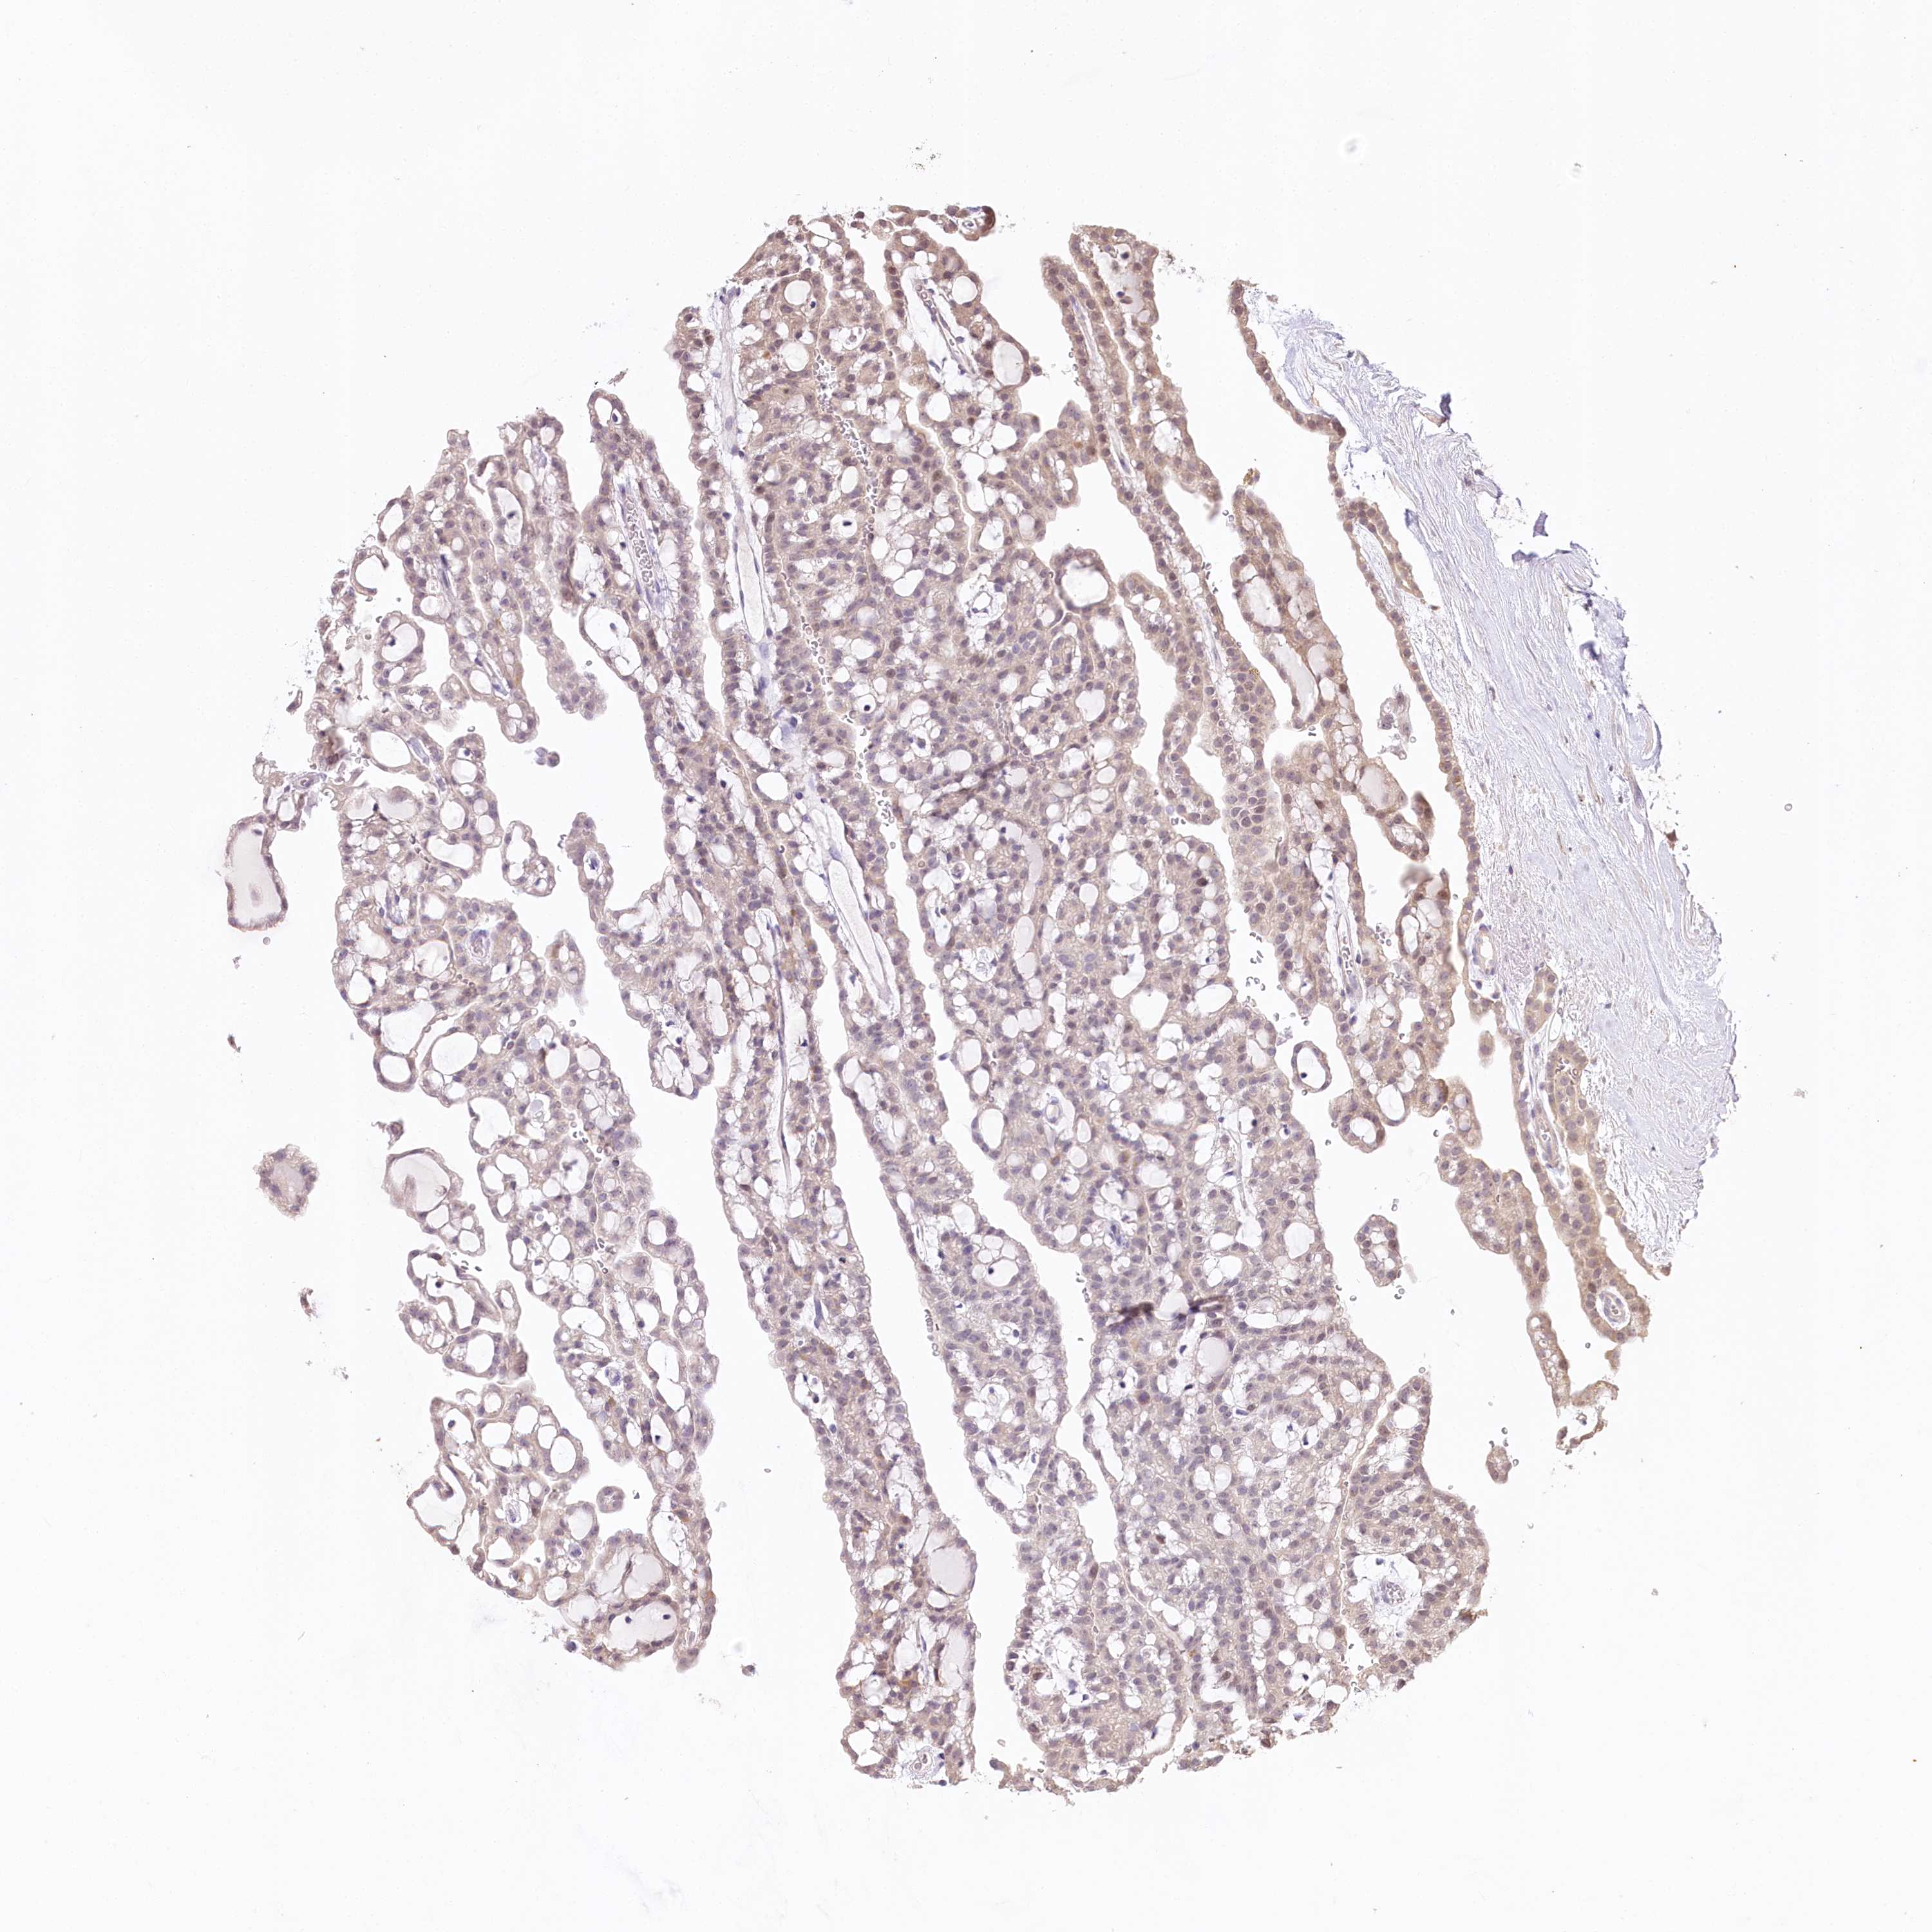

KIDNEY CHROMOPHOBE (TCGA) - Interactive survival scatter ploti

The Survival Scatter plot shows the clinical status (i.e. dead or alive) for all individuals in the patient cohort, based on the same data that underlies the corresponding Kaplan-Meier plots. Patients that are alive at last time for follow-up are shown in blue and patients who have died during the study are shown in red.

The x-axis shows the expression levels (FPKM) of the investigated gene in the tumor tissue at the time of diagnosis. The y-axis shows the follow-up time after diagnosis (years). Both axes are complimented with kernel density curves demonstrating the data density over the axes. The top density plot shows the expression levels (FPKM) distribution among dead (red) and alive patients (blue). The right density plot shows the data density of the survived years of dead patients with high and low expression levels respectively, stratified using the cutoff indicated by the vertical dashed line through the Survival Scatter plot. This cutoff is automatically defined based on the FPKM cutoff that minimizes the p-score. The cutoff can be changed by dragging the vertical line or by entering a cutoff value in the square labeled "Current cut-off".

Under the Survival Scatter plot the p-score landscape (black curve; left axis) is shown together with dead median separation (red curve; right axis). Dead median separation is the difference in median mRNA expression between patients who have died with high and low expression, respectively. It is calculated as follows: median FPKM expression of dead patients with high expression - median FPKM expression of dead patients with low expression. This is intended to aid the user in visually exploring custom cutoffs and the associated p-scores and dead median separation.

Individual patient data is displayed and can be filtered by clicking on one or more of the category buttons on the top of the page. Categories describing expression level and patient information include: high, low, alive, dead, female, male and tumor stages. The scale of the x-axis can be toggled between linear and log-scale by clicking on the "x log" button. Mouse-over function shows TCGA ID, patient information and mRNA expression (FPKM) for each patient.

& Survival analysisi

Kaplan-Meier plots summarize results from analysis of correlation between mRNA expression level and patient survival. Patients were divided based on level of expression into one of the two groups "low" (under cut off) or "high" (over cut off). X-axis shows time for survival (years) and y-axis shows the probability of survival, where 1.0 corresponds to 100 percent.

ZNF226 is not prognostic in Kidney Chromophobe (TCGA)